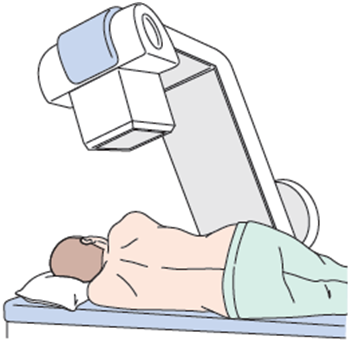

- レントゲンで確認しながら、専用の針で「ヘルニコア®」という薬剤を注入します。

- 治療自体は順調にいけば10-15分程度で終了します。